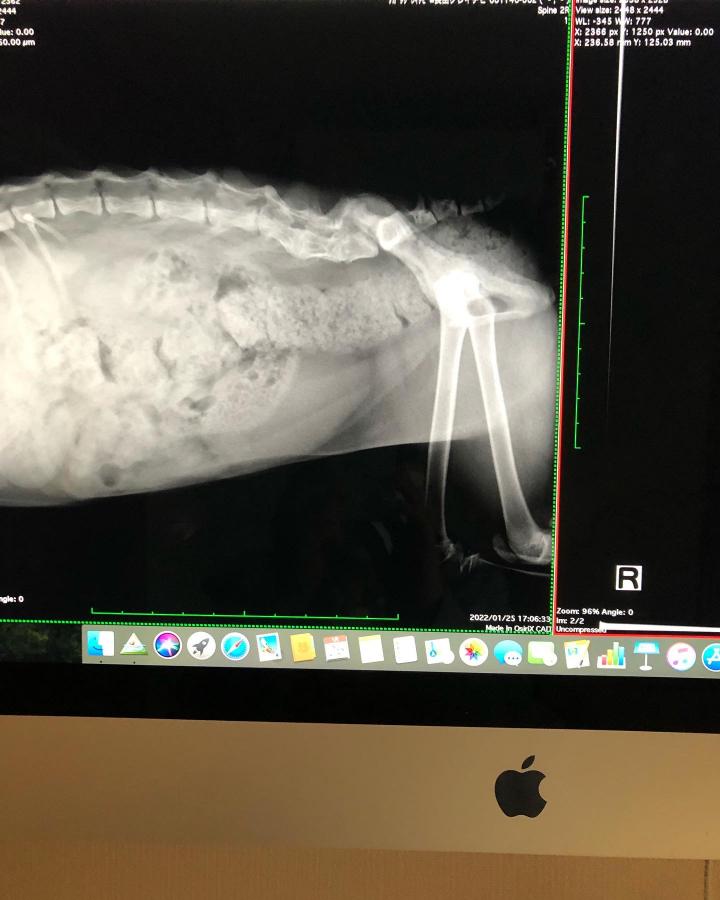

昨日ちぃちゃんの下半身の精密検査のお話&定期検診に行ってきました。

精密検査前のレントゲンも撮りました。

567がくっついてしまっているということで、やはりCT.MRIが必要のようです💦